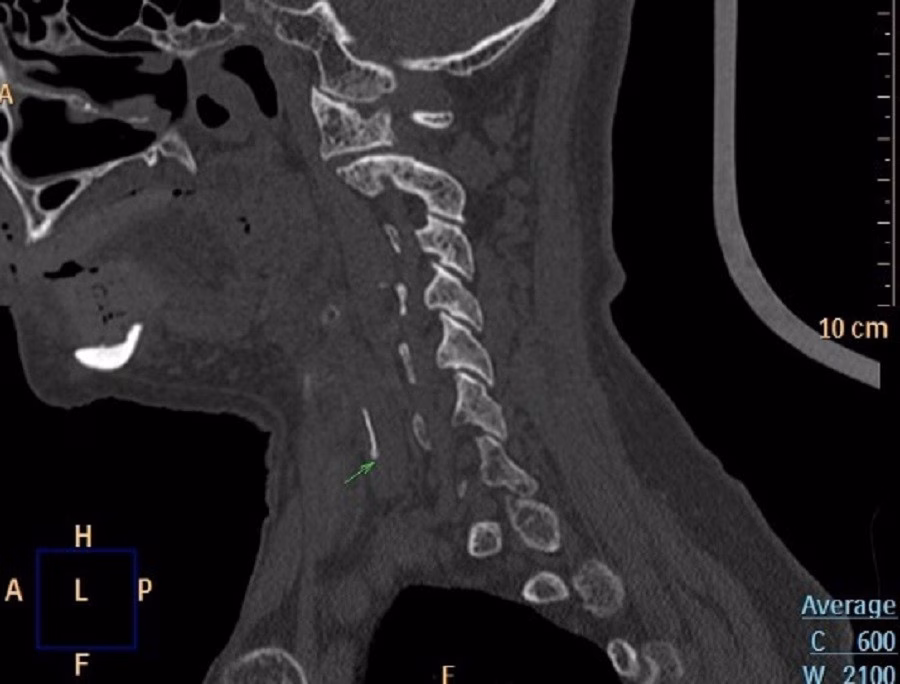

Một bà cụ 85 tuổi, có tiền sử tăng huyết áp và tiểu đường, sau bữa ăn cá cảm thấy nuốt vướng và đau họng. Thay vì tới bệnh viện, bà đã cố gắng nuốt cơm liên tục và dùng tay móc họng với hy vọng “đẩy” xương cá ra. Sau vài ngày, cơn đau không giảm mà còn nặng hơn, khiến bà khó ăn uống. Khi tới Bệnh viện Thống Nhất, nội soi Tai Mũi Họng phát hiện phù nề nghiêm trọng ở vùng sụn phễu trái; X‑quang và CT cho thấy một mảnh xương cá dài khoảng 1×22 mm đã xuyên ra khỏi ống tiêu hoá và cắm sâu vào thùy trái tuyến giáp.

Bác sĩ đã quyết định phẫu thuật mở cổ để lấy dị vật, đồng thời cho bệnh nhân dùng kháng sinh, kháng viêm và thuốc giảm đau. Nhờ can thiệp kịp thời, bệnh nhân đã ổn định và ra viện sau vài ngày.